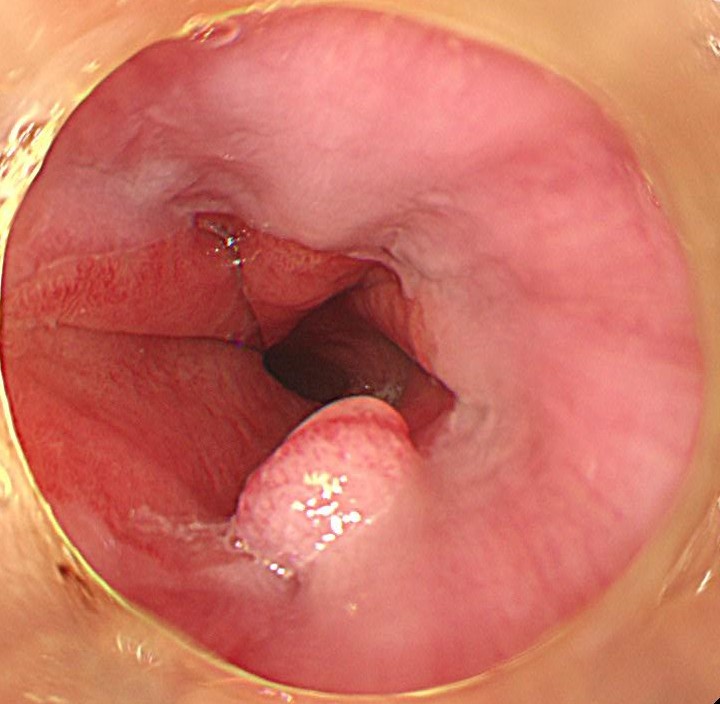

嚥下障害を有する若年女性の患者さん:胃内視鏡しますと、バレット食道 (SSBE) とその境界にポリープを認めます。

狭帯域光 (NBI) 観察しますと、腫瘍血管は認めず、良性の炎症性ポリープと診断しました。有症状であり、また今後のがん化のリスクも否定できない (エビデンスレベルは低いですが) ため、治療対象と判断しました。